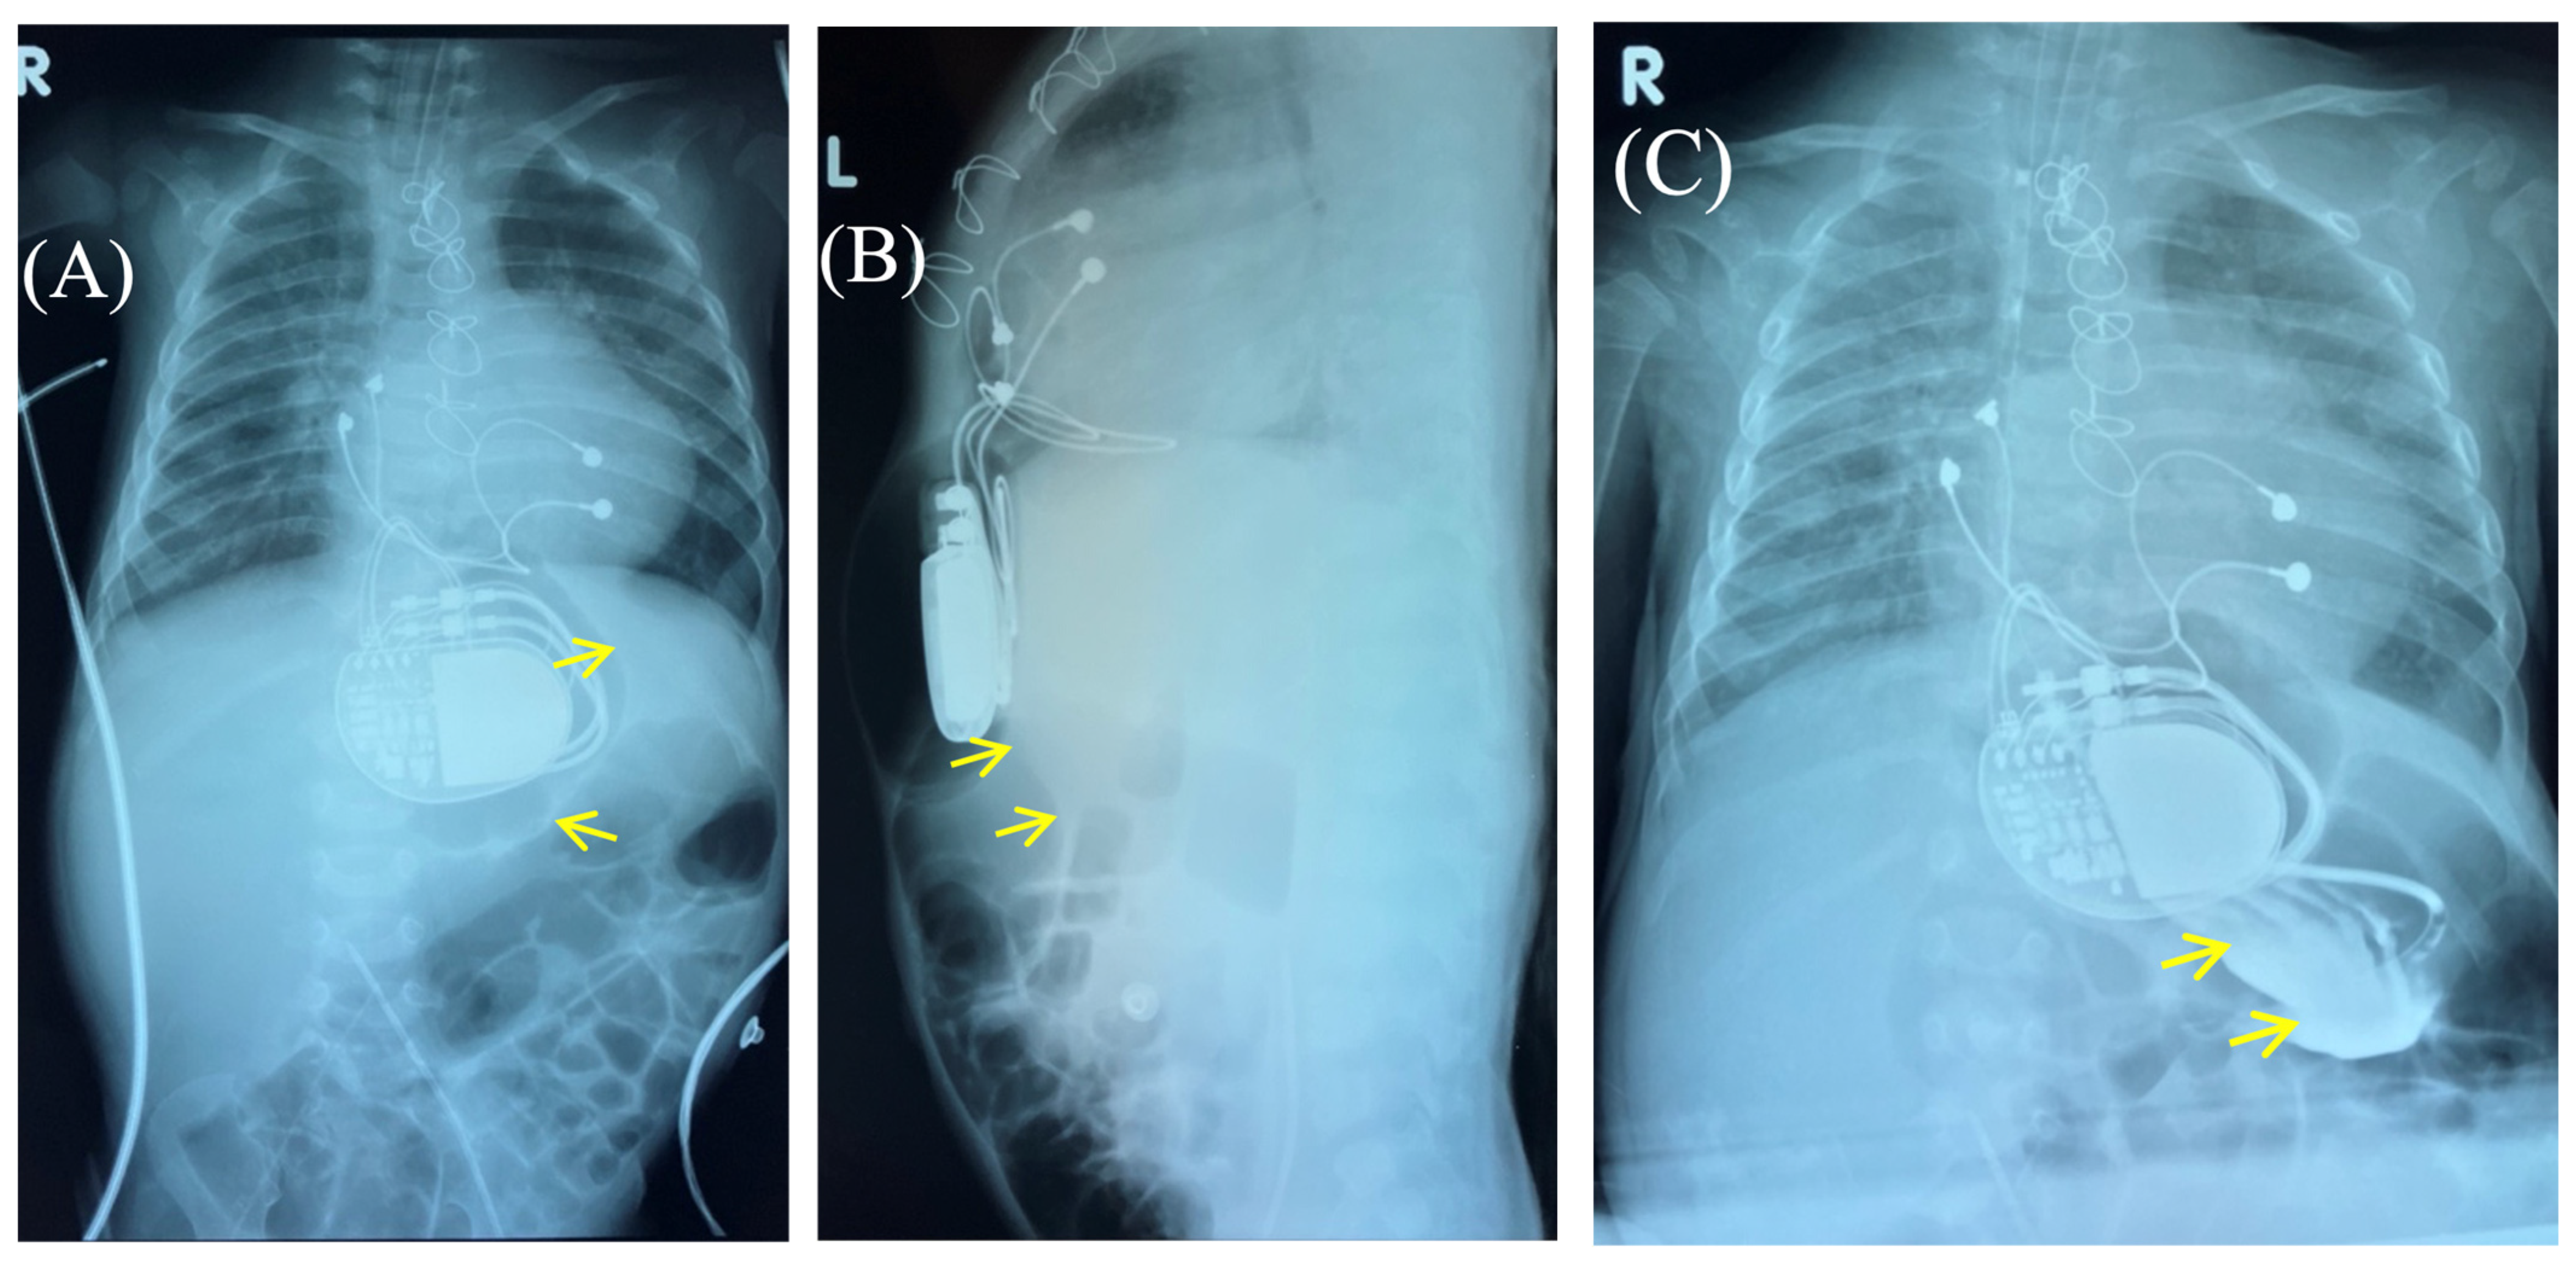

Based on the results of three wound cultures, no pathogenic flora were detected. On the seventh day, the wound was sutured, and healing proceeded without complications. The wound healed seven days after suture closure. A follow-up chest and abdominal X-ray revealed no signs of pneumothorax, pneumomediastinum, or free air in the upper anterior abdominal wall along the midline in the projection of the pacemaker pocket (Figure 6).

Figure 6. Chest X-ray after surgery debridement and closure of the wound. Chest X-ray (frontal (A) and lateral (B) view) shows no signs of pneumothorax, pneumopericardium, pneumomediastinum with minimal air at the pacemaker pocket site. (C) The healed sternotomy and the projection of the pacemaker pocket 12 days after revision and sanitation.